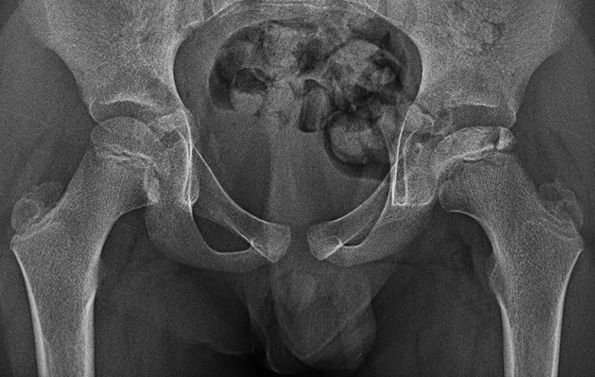

ペルテス病は股関節が痛む病気で、早期に診断しないと大腿骨頭の変形が進行してしまいます。MRIが早期診断に有効ですが、身体を触れて詳しく診察し、注意深くレントゲン写真を見ることが、診断の第一歩です。

図1:Case courtesy of Jeevan K Karuppannan, Radiopaedia.org, rID: 184614

図1:7歳、 男児、 左ペルテス病